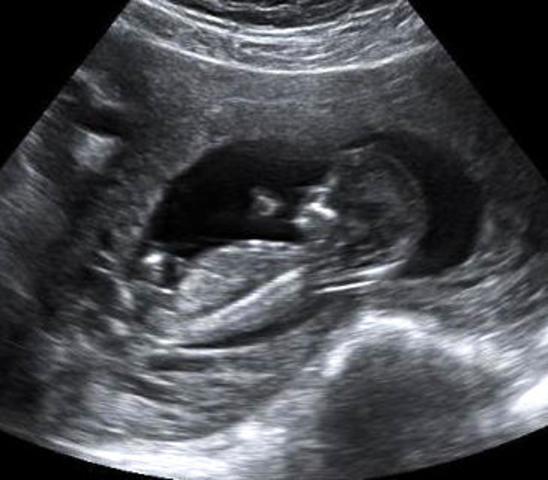

Tercer mes

Esta es la última semana del primer trimestre. Las posibilidades de aborto son mucho menores. Todos los órganos están formados y a partir de aquí solo tienen que evolucionar para permitir al bebé sobrevivir fuera del útero materno. Ya se puede determinar el sexo del bebé.